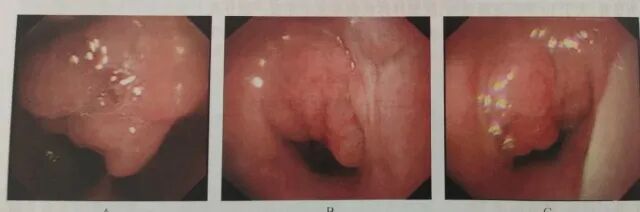

(图:由电子鼻咽镜可见腺样体肥大)

通过鼻咽部侧位片或鼻咽部CT检查,结合患儿临床症状即可明确诊断腺样体肥大。CT检查能够更准确评估腺样体肥大的程度并同时显示鼻腔鼻窦情况,为临床常用的检查手段。此外亦可通过电子鼻咽镜直接观察腺样体肥大的情况。